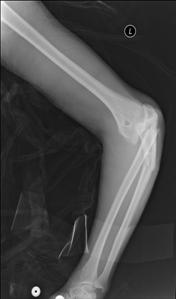

TRAUMATISMELE EXTREMITATILOR

Fractura de humerus

Fracturi simple: SPIRALA OBLICA TRANSVERSALA

Fractura spirala de Fractura transversa de diafiza femurala Fractura spirala de diafiza tibiala

diafiza humerala

Fractura spirala de diafiza tibiala Fractura oblica de diafiza tibiala Fractura transversala de diafiza tibiala